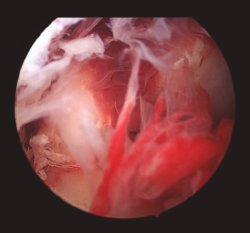

Figura 3. Imagen intraoperatoria artroscópica que muestra el abundante tejido esfacelar en un caso de artritis séptica de rodilla.

Cuando la infección ya se ha producido, el tratamiento de elección debe ser realizado tan pronto como sea posible y en cuanto haya sospecha clínica de infección, refrendada o no por los resultados de las pruebas complementarias, los cuales no justifican una demora en la actuación. Este tratamiento consiste en asociar un desbridamiento artroscópico agresivo al inicio del tratamiento antibiótico(4,5,9). Durante el desbridamiento artroscópico es obligatorio recoger muestras para el cultivo antes de la administración de antibióticos, y ambas terapias deben realizarse lo antes posible. La artroscopia debe incluir lavado extensivo con suero, desbridamiento de tejido desvitalizado, eliminación de fibrina, coágulos y sinovectomía (Figuras 3 y 4).

Figura 4. Imagen intraoperatoria artroscópica que muestra el aspecto de la plastia de LCA tras el desbridamiento del tejido sinovial.

También se sugiere eliminar la capa de fibrina que cubre la superficie del injerto y evaluar la integridad macroscópica del injerto, así como su tensión. No es necesario retirar la plastia en todos los casos, debiendo reservarse esta actuación para aquellos casos en los que se objetive un claro fracaso en su funcionalidad, aspecto séptico durante la artroscopia o persistencia de la infección pese al tratamiento correcto(4).